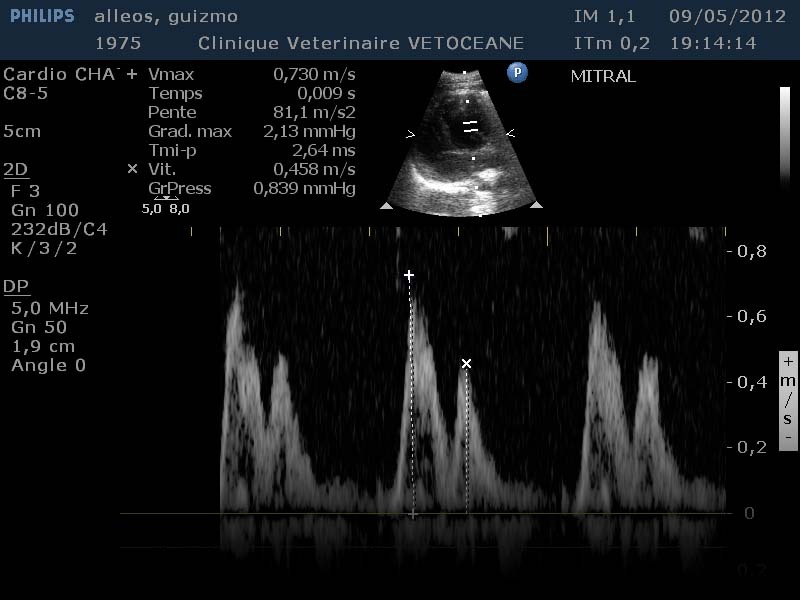

- Un examen BD, TM, Doppler, couplés à un ECG chez le chien

- Un examen BD, TM et Doppler chez le chat

- un examen BD, TM et généralement Doppler chez les NAC

- Doppler pulsé, continu et couleur